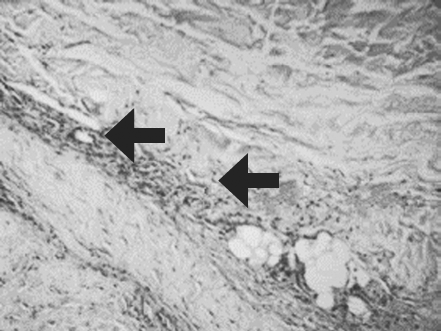

Histological examination of biopsy samples taken from the area of ATMSC transplantation for all the patients revealed the presence of pronounced vascularization with the perifocal proliferation of fibroblasts in both the superficial and deep layers of the dermis (Fig. 6, 7). An immunohistochemical study revealed that the use of ATMSCs resulted in a 5.6-fold increase in the expression of proliferation markers of epithelial and connective tissue cell lines in the injection area (p < 0.01) (proliferation 2.1–2.2), and that apoptotic activity was completely suppressed (Fig. 8, 9). Laser Doppler flowmetry assessment of the microcirculation in the area of stem cell injection on day 7 after early necrectomy, skin grafting, and the administration of MMSCTM showed double the average level of perfusion and mean square deviation of the amplitude of blood flow oscillations than for areas where MMSCTM was not used (p < 0.05) (Table 6).

Fig. 7. Patient E., 49 years old, 5th day of observation. Newly formed vessels with perifocal proliferation of fibroblasts. Color in gof hematoxylin-eosin. Zoom ×400

Рис. 7. Пациент Д., 49 лет, 5-е сутки наблюдения. Новообразованные сосуды с перифокальной пролиферацией фибробластов. Окраска гематоксилином и эозином. Увеличение ×400